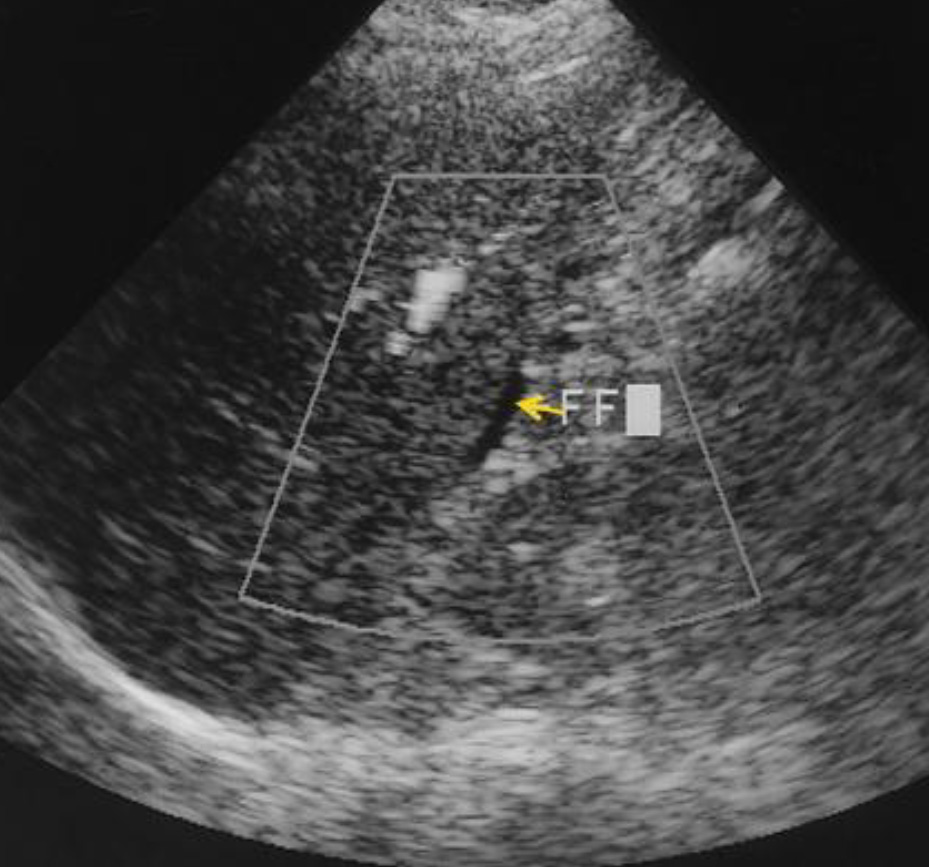

Медицина и диагностика: Инвазивный пузырный занос на УЗИ

Раздел: Альбом идей